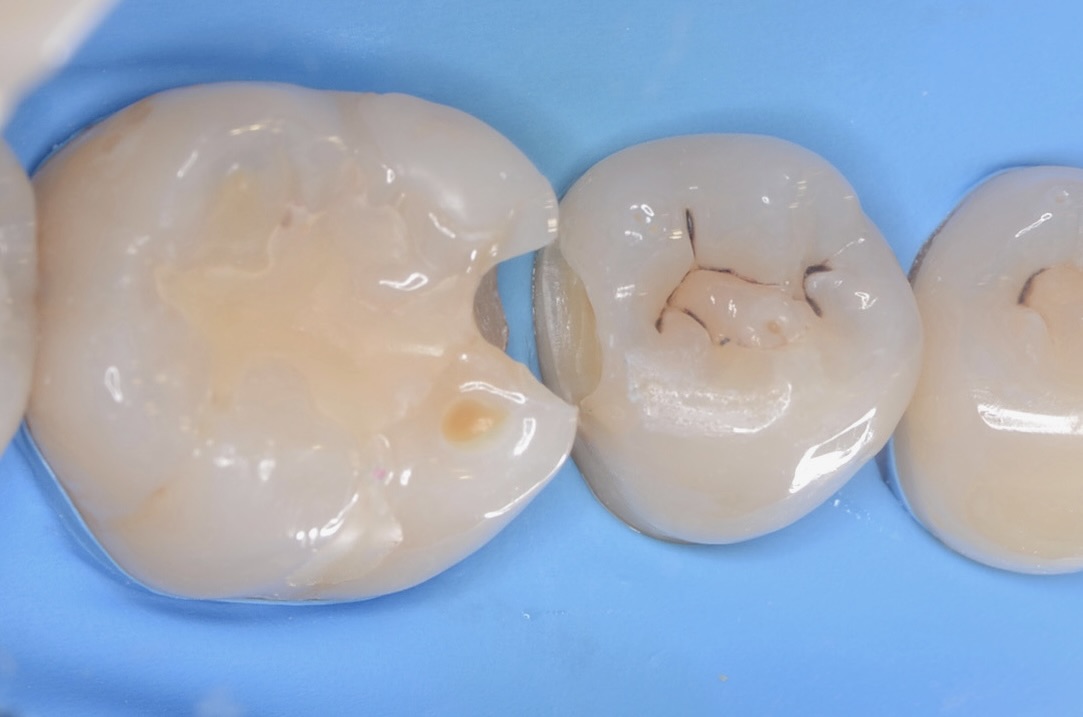

5番遠心

虫歯を取り除いたところです。 -

拡大

5番の辺縁隆線を削らないよう、最小限の切削量で治療します。 -